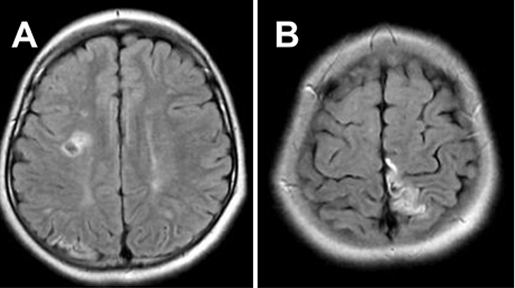

8岁的太一因为右腿运动无力就医,磁共振血管造影(MRA)显示双侧脑梗死,在 Willis 环周围分层双侧血管狭窄闭塞,确诊为烟雾病。

患者初次就诊时进行的 FLAIR MRI,显示 MMD 引起的双侧脑梗死

患者初次就诊时进行的MRA